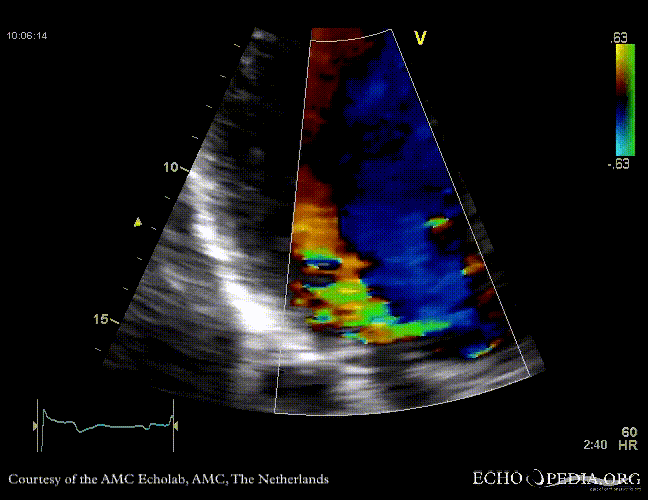

Case 10